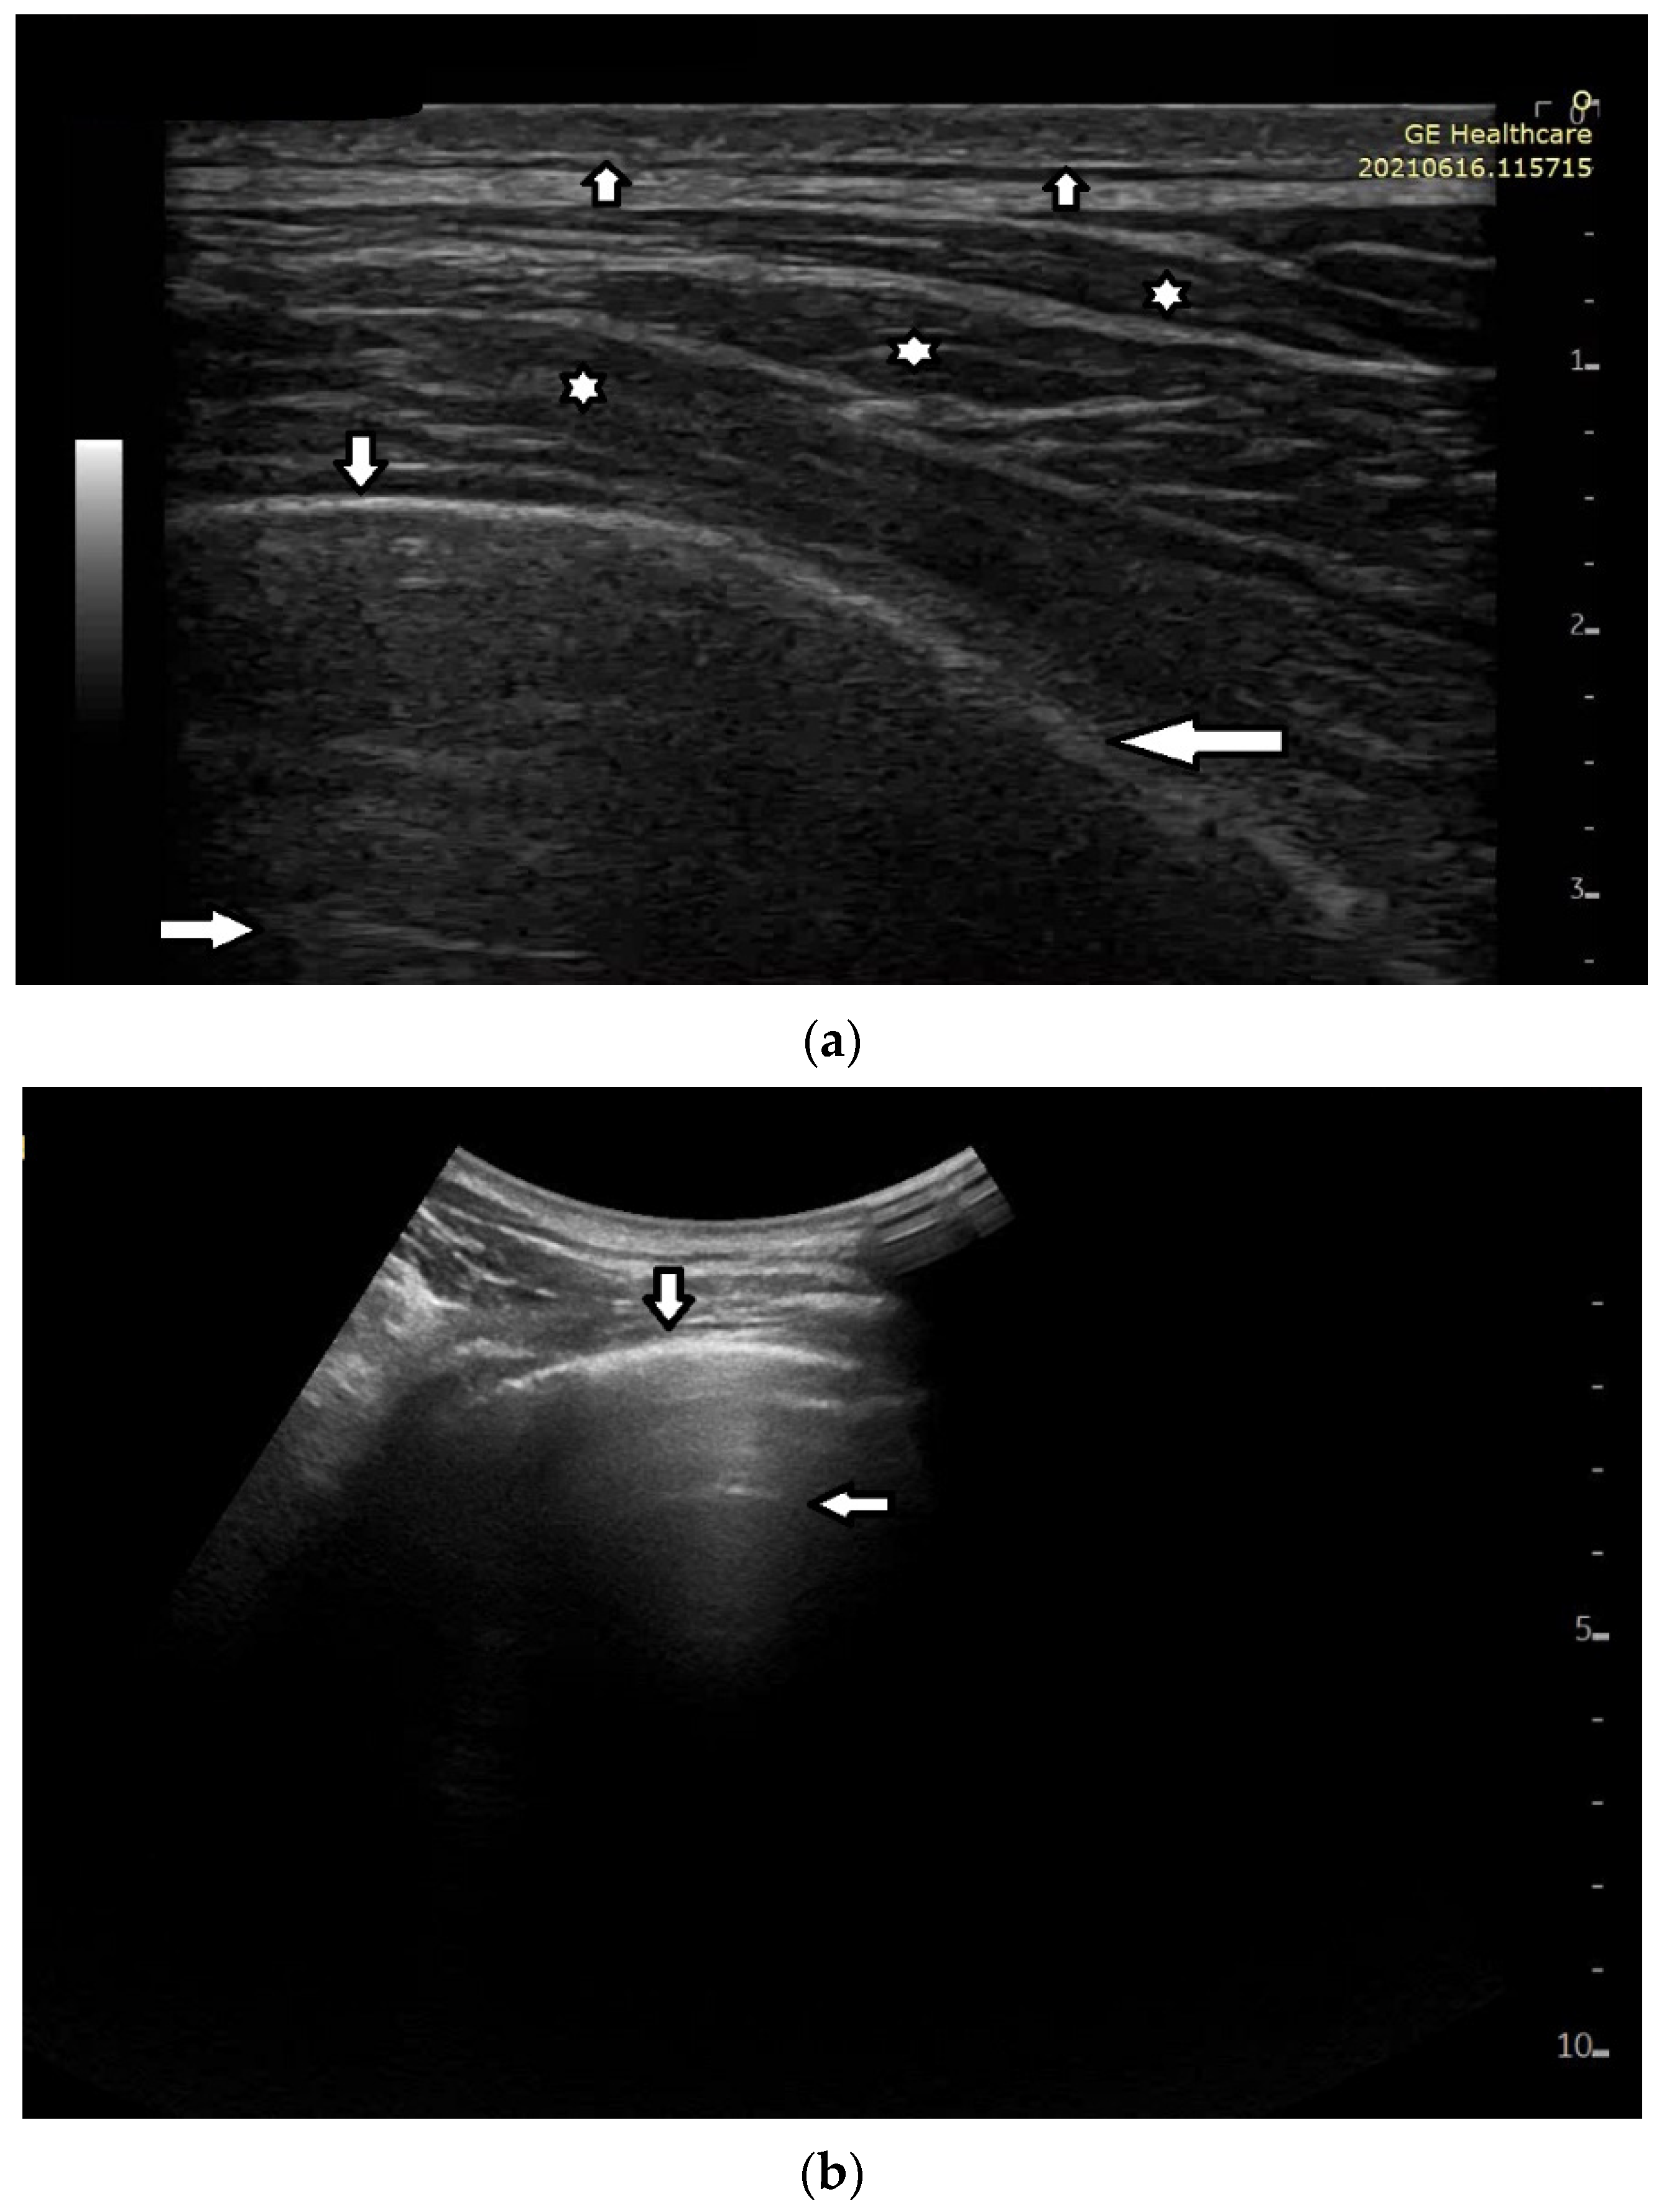

In healthy individuals, an ultrasound examination of the lungs visualizes only the lung surface, termed the pleural line (see Figure 2a). A-line artifacts are visible below the pleural line. These form horizontal lines that appear at regular intervals, equaling the distance between the body surface and the pleural line (see Figure 2b). Under anatomical conditions, it is not possible to visualize lung parenchyma and the interstitium. Only when subpleural areas of the lungs lose their aeration due to lesions can vertical artifacts and/or subpleural consolidations be observed [7]. Why is this so?

Figure 2.

(a) Lung ultrasound, linear probe: white stars (*) muscles of the chest wall; down arrow (↓) well-defined pleural line (perpendicular ultrasound beam); left arrow (←) blurred pleural line secondary to the tangential incidence of the ultrasound beam; up arrow (↑) subcutaneous tissue; right arrow (→) A line, horizontal artifact. (b) Lung ultrasound, convex probe: down arrow—pleural line, smooth, echoic and regular; left arrow—A-line artifact.

- Answer 2:

Once an US pulse reaches the pleura plane through the chest wall, it is partially reflected toward the probe and partially transmitted to the channels provided by a specific distribution of the aerated spaces, which characterizes the outer lung surface. In a healthy lung, the size of the interalveolar septa is, and reasonably so, supposed to be comparable to a capillary lumen (less than 10 microns), and an US pulse “sees” this aerated space distribution as a compact air wall. In this case, the acoustic energy is essentially reflected back to the probe. The lung surface is highlighted with a thick white line (the so-called pleural line), and A-line artifacts are visible below the pleural line thanks to the multiple reflections of the acoustic wave between the lung surface and the probe. Replicas of the thoracic wall structures are also often well visible between every pair of A lines thanks to the replica and mirror effects as a consequence of the strong reflection of the lung surface. It is worth noting, however, that the affirmation “The A line artifacts form horizontal lines that appear at regular intervals equaling the distance between the body surface and the pleural line” is not entirely correct. Such an affirmation is correct only if the pleural plane is exactly parallel to the head of the probe [8].

On the other hand, in the presence of thickened interstitial spaces, the pulse energy can be partially trapped by the latter. This can subsequently be reradiated toward the probe after multiple reflections between the separated aerated spaces, giving rise to vertical artifacts, which arise from the pleura line. The imaging parameters play a fundamental role in the formation of the artifacts, and the visibility of a vertical artifact (that is, its brightness, lateral dimension, and length) depends on multiple non-orthogonal factors including the gain, the time gain compensation (TGC), and all the parameters that can be easily set by the operator from the scanner keyboard. The clinical information that can be obtained from lung US images is essentially artifactual information except in the case of consolidation when anatomical information is obtained.